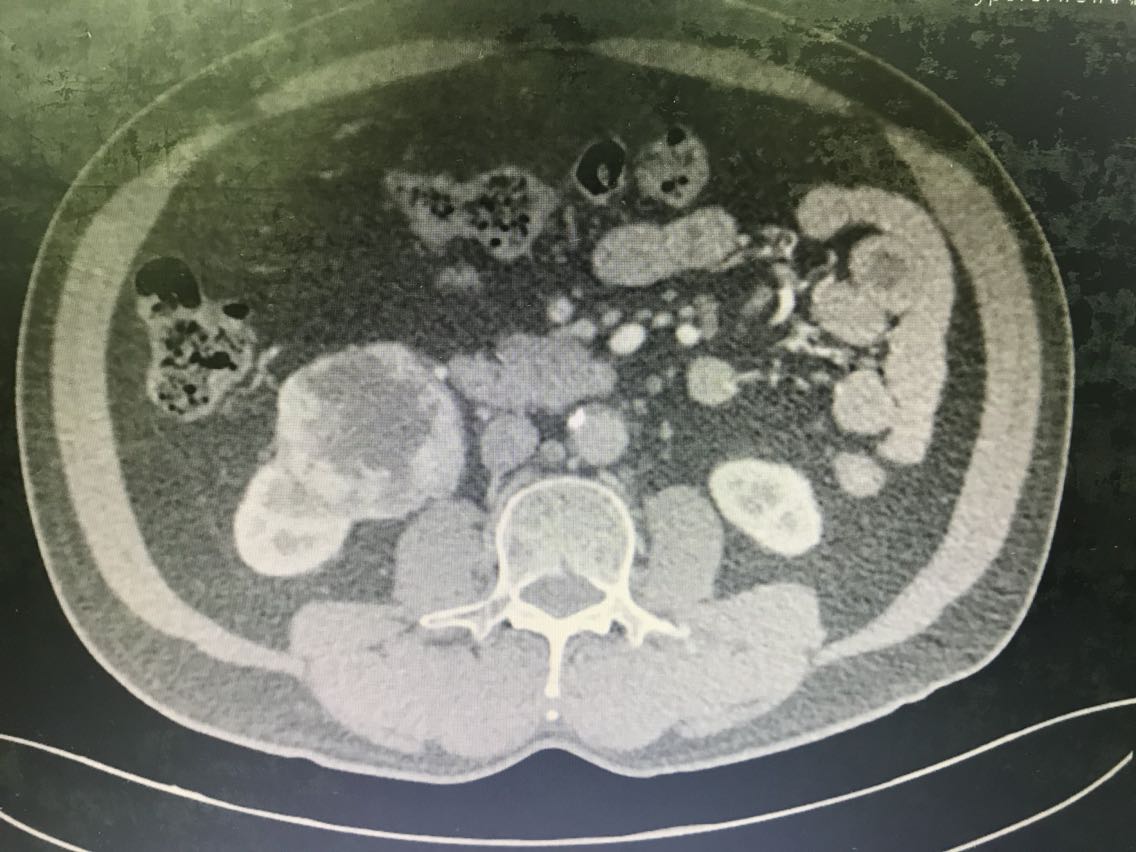

患者男性,62岁。 主诉:咯血、体检发现右肾占位1+月 现病史:1+月前,患者无明显诱因出现反复咯血,为痰中带鲜血,无胃内容物,无畏寒、发热,无胸闷、胸痛,无潮热盗汗,无恶心、呕吐,无腹胀、腹痛等不适。于当地医院就诊,行相关检查(具体报告未见)考虑“支气管扩张”,行相关治疗(具体不详)后患者咯血症状好转出院。患者于住院期间检查发现右肾占位(报告未见),无腰痛、腰胀,无血尿、蛋白尿,无尿少及排尿困难。患者为进一步诊治,于我院门诊就诊,查肝肾功能、肿瘤标志物、小便常规未见明显异常。上腹部增强CT:右肾前下份占位,考虑透明细胞癌(T3aN2Mx),左肾结石、囊肿,腹膜后多发淋巴结,肝脏右后叶下段小囊肿,腹主动脉管壁钙化。现患者为进一步明确诊断及治疗,入住我科。 既往史无特殊。

查体无特殊。 辅助检查: 心电图:窦性心律,电轴左偏,左前分支阻滞,不完全性右束支阻滞。 上腹部增强CT:右肾前下份占位,考虑透明细胞癌(T3aN2Mx),左肾结石、囊肿,腹膜后多发淋巴结,肝脏右后叶下段小囊肿,腹主动脉管壁钙化。

诊断:1、右肾肿物:肿瘤可能性大,其他?;2、支气管扩张。 治疗:腹腔镜根治性右肾切除 术中见右肾前下份可见肾脏肿物,大小约6.1*5。8cm,病变突出右肾轮廓外,未见明显的突破肾周筋膜。与肾周组织、右侧肾静脉、右侧输尿管上段粘连明显。

患者术前CT提示右肾肿瘤T3aN2Mx,术中剖视标本见肿瘤未超过肾周筋膜,但最终分期需等待术后病理诊断。可能会出现临床分期过高的情况。